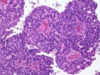

What tumor type is shown here?

* key features?

Papillary Adenocarcinoma

• MULTIFOCAL, Granular appearance is key

hemorrhage and necrosis may also be seen here but is less common than renal cell carcinoma

What is shown here?

• What are the KEY features?

- Well-circumscribed, often with distinct fibrous capsule

- PAPILLARY - little finger like projections in the cellular arrangment

- Have papillary FIBROVASCULAR CORES (seen in center)

- Foamy macrophages (clear cells) in papillary cores and intracellular hemosiderin are sensitive/specific features